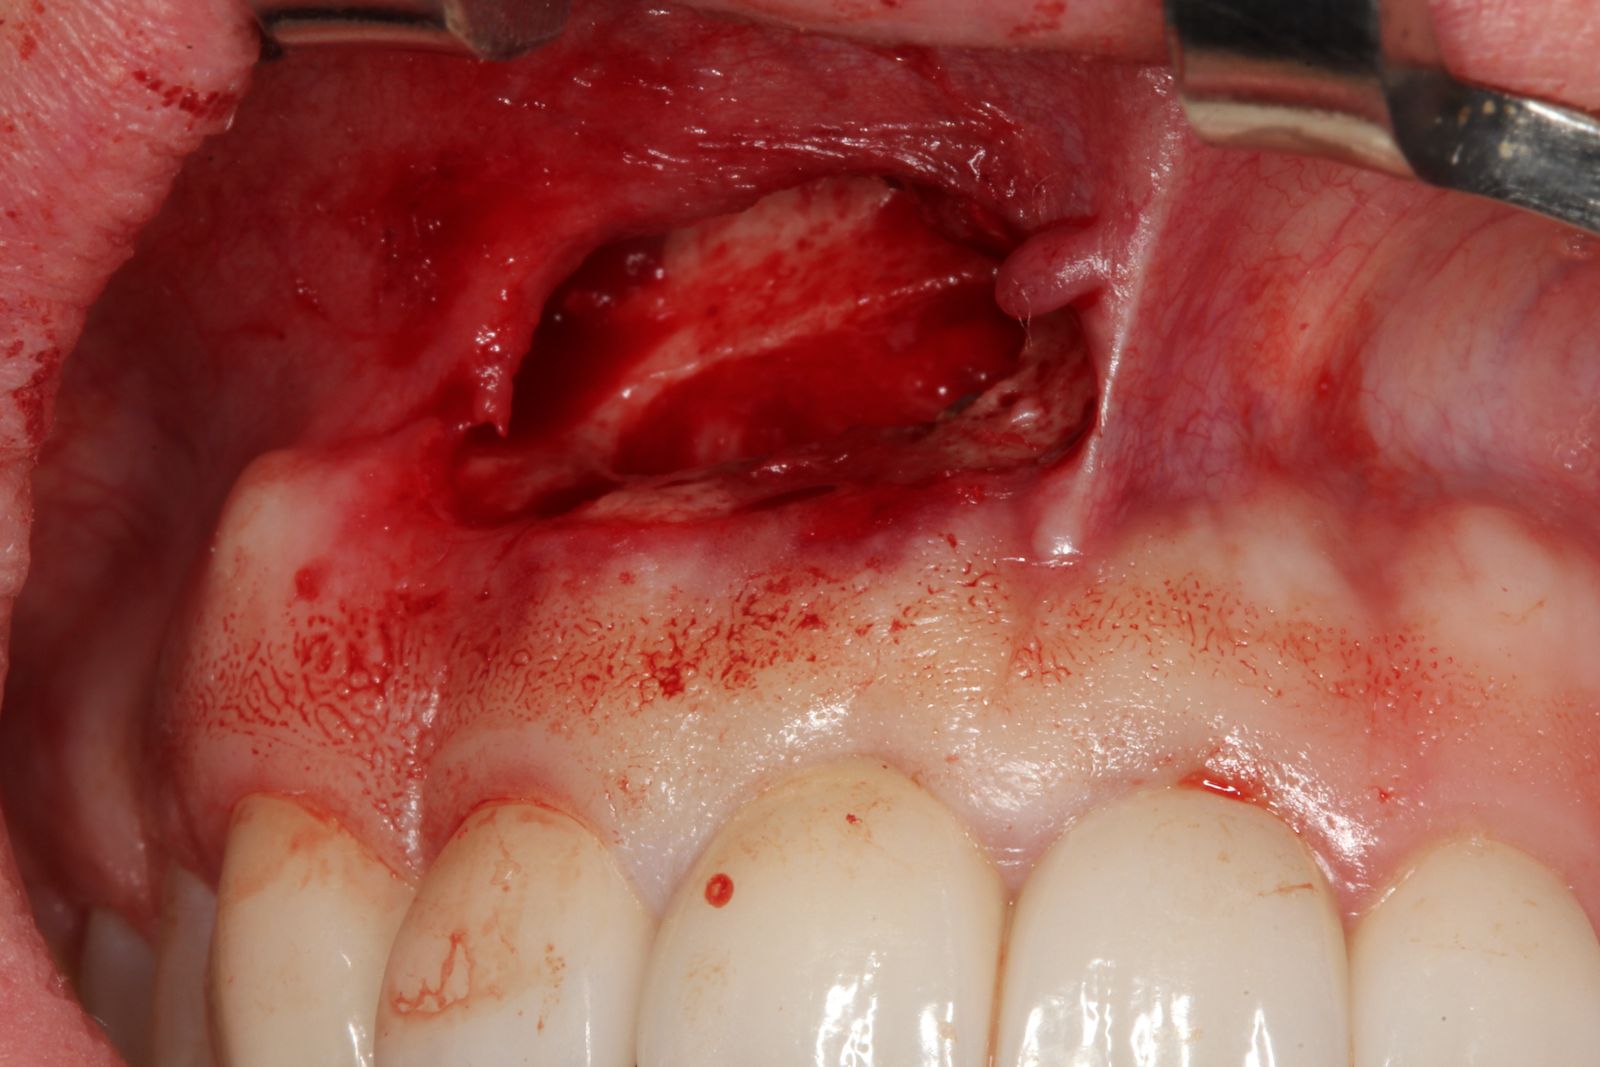

Uma incisão na gengiva com bisturi, permitindo acesso à região óssea. A exposição da área infectada muitas vezes já revela a gravidade da lesão, seguida da drenagem do conteúdo infeccioso, quando presente.

Depois, é feita uma curetagem cuidadosa, removendo todo o tecido inflamado ou contaminado ao redor da raiz e o corte da ponta do ápice radicular, eliminando a porção comprometida. Com a área limpa, pode-se aplicar o enxerto ósseo, geralmente com biomaterial associado a técnicas modernas de regeneração.